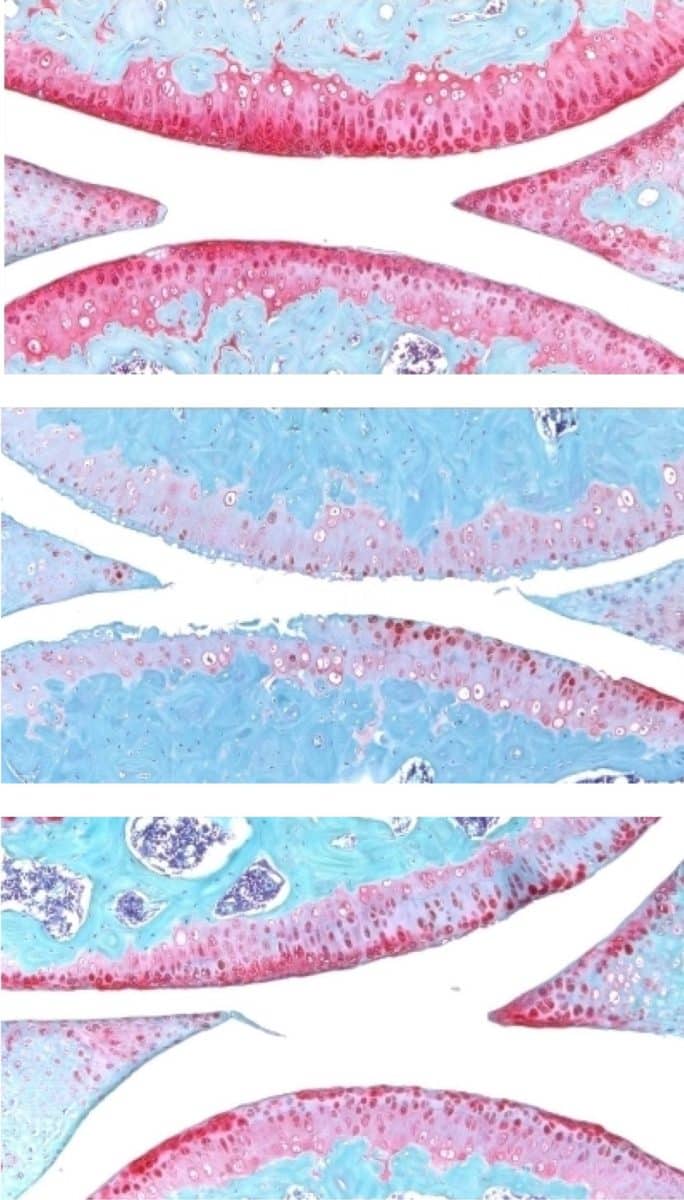

Ученые проверили разработку на образцах человеческой ткани после операций по замене коленного сустава. Эти образцы включали внеклеточный матрикс в суставе и клетки хондроцитов, генерирующие хрящ. Они отреагировали на лечение, образуя новый, функциональный хрящ.

Белок 15-PGDH, также известный как герозим, — это фермент, который с возрастом становится более активным. Этот фермент обнаружили эти же исследователи в 2023 году. Белок также приводит к потере функции тканей. Заблокировав функции 15-PGDH с помощью небольшой молекулы, исследователи выяснили, что это приводит к увеличению мышечной массы и выносливости старых животных. Экспрессия 15-PGDH у молодых мышей, напротив, привела к сокращению и ослаблению их мышц. Герозим также участвует в регенерации костей, нервов и клеток крови.

Результаты исследования показали, что можно регенерировать хрящ, потерянный из-за старения или артрита, с помощью перорального препарата или местной инъекции. Это избавляет пациентов от замены коленного и тазобедренного суставов. Препарата сейчас находится на стадии клинических испытаний.